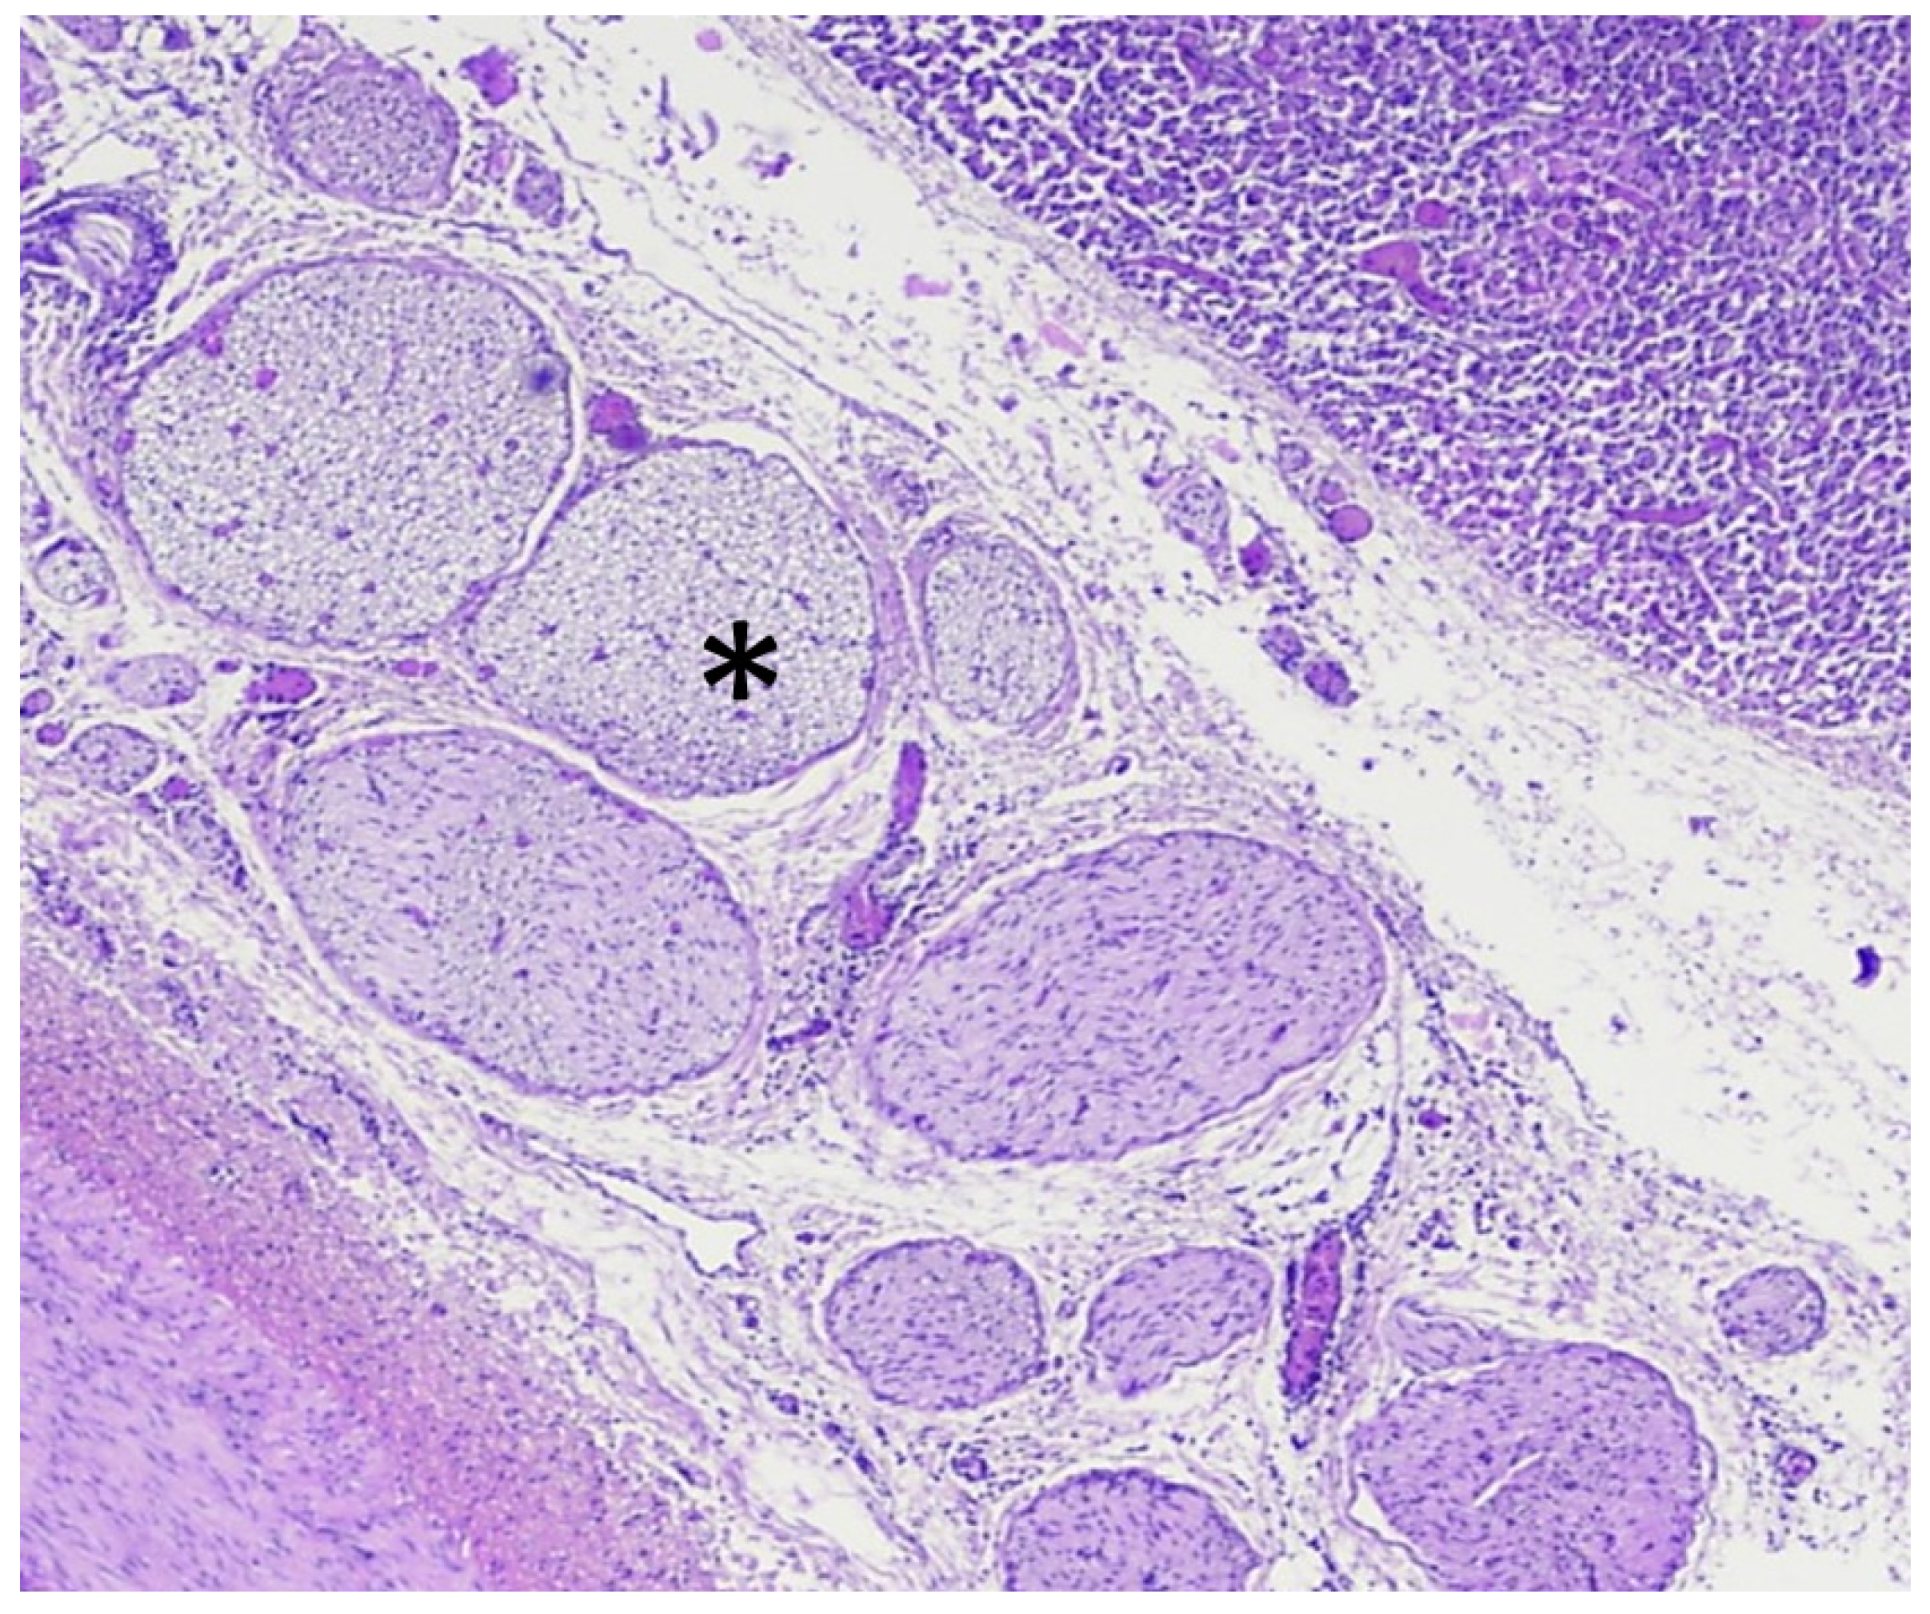

3.3. Analysis of HIFU Treatment